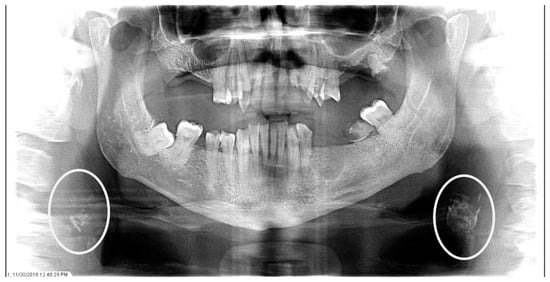

The characteristics of the CAC patients are presented in Table 1. Between 2014 and 2023, there were 559 patient records with the terms “carotid artery calcification” or “carotid” or “calcification of the carotid artery” noted. After the panoramic radiographs were reviewed, 314 patients were confirmed to have a diagnosis of CAC (including 26 patients with a history of carotid endarterectomy). The remaining 245 patient records were excluded because of the absence of detectable CAC on PRs and the absence of PRs to review. The ages ranged from 29 to 92 years, with a median of 68 years. CAC was most prevalent (39.5%) in the seventh decade of life. There were 168 (53.5%) female and 146 (46.5%) male patients. The median age of the female patients was 68 years, and the median age of the male patients was 69.5 years. The calcifications were identified unilaterally in 168 (53.5%) patients (88 females/80 males; mean age: 67.8 years) (Figure 1 and Figure 2) and bilaterally in 146 (46.5%) patients (80 females/66 males; mean age: 68.6 years) (Figure 3, Figure 4 and Figure 5). The DMFT index in the CAC patients ranged from 8 to 32 (mean = 26.6). The frequency of patients with CAC with a history of hypertension, hyperlipidemia, diabetes mellitus, CVA, and CAD was 86.2%, 57.6%, 30.7%, 15.5%, and 28.7%, respectively.

Figure 3.

The panoramic radiograph of an 80-year-old male patient with a medical history of hyperlipidemia and diabetes mellitus showing bilateral carotid artery calcifications (CACs) during a comprehensive dental examination. The CACs are encircled by a white line.